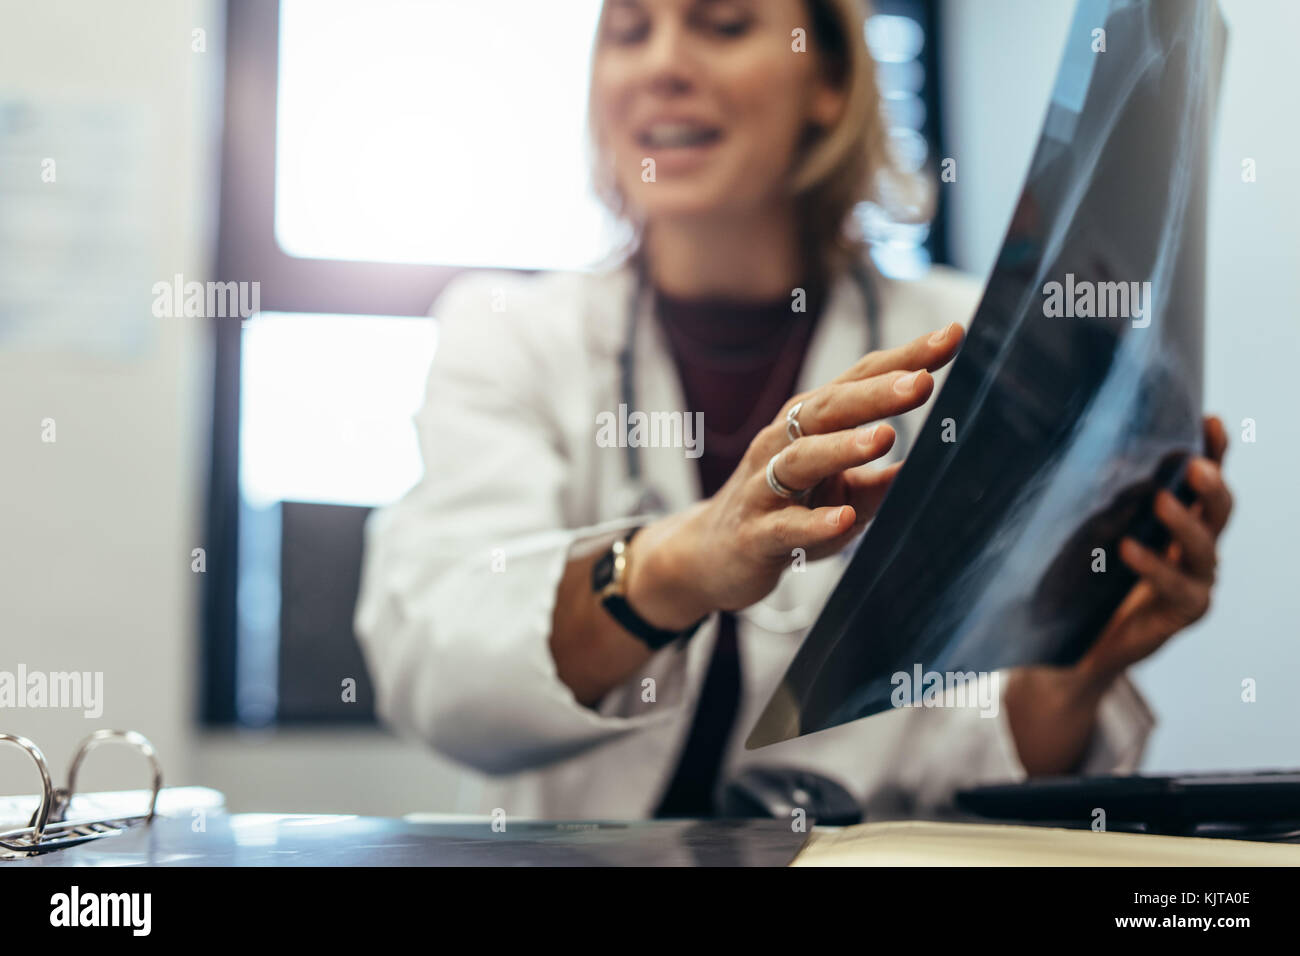

Medical doctor explaining medical scan result to patient in clinic. Medicine practitioner with x-ray discussing diagnosis. Stock Photohttps://www.alamy.com/image-license-details/?v=1https://www.alamy.com/stock-image-medical-doctor-explaining-medical-scan-result-to-patient-in-clinic-166491822.html

Medical doctor explaining medical scan result to patient in clinic. Medicine practitioner with x-ray discussing diagnosis. Stock Photohttps://www.alamy.com/image-license-details/?v=1https://www.alamy.com/stock-image-medical-doctor-explaining-medical-scan-result-to-patient-in-clinic-166491822.htmlRFKJTA0E–Medical doctor explaining medical scan result to patient in clinic. Medicine practitioner with x-ray discussing diagnosis.